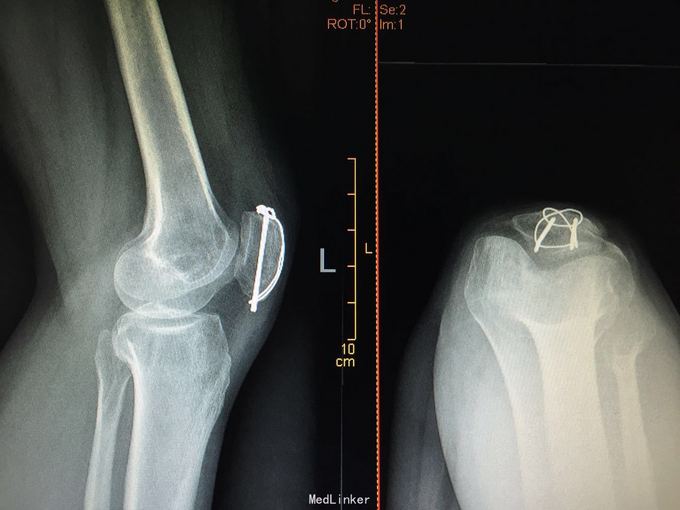

髌骨骨折切开复位克氏针张力带内固定

摔伤致左膝部肿痛活动受限2小时。 46岁女性,行走时不摔摔伤,左膝跪地

左髌骨骨折 急诊行切开复位克氏针张力带内固定术